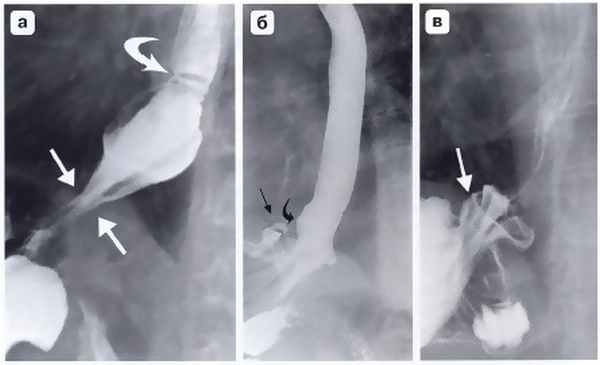

Другим важным и довольно частым осложнением операции фундопликации по Ниссену является соскальзывание кардиального отдела и дна желудка с терминальным отделом пищевода относительно манжетки (рис. 4, б). Как правило, причиной этому служит прорезывание швов между манжеткой и пищеводом. Ушивание ножек диафрагмы при укорочении пищевода и фиксация к ним антирефлюксной манжетки также приводят к «соскальзыванию», поскольку пищевод, сократившись после операции, втянет за собой кардию вместе с расправленной манжетой в заднее средостение. Рентгенологически это выглядит в виде феномена «песочных часов», когда одна часть манжетки находится выше диафрагмы, а другая — ниже (рис. 5). Осложнение сопровождается выраженной дисфагией, регургитацией и изжогой, что, безусловно, требует повторной корригирующей операции. Частой ошибкой при использовании эндоскопической техники является использование тела или даже антрального отдела желудка при формировании антирефлюксной манжетки (см. рис. 4, в). Если короткие желудочные сосуды не пересечены, хирург вынужден использовать при фундопликации на 360° не дно желудка, а переднюю его стенку. Все это ведет к перекруту, выраженной деформации желудка, который, по понятным причинам, не способен выполнять антирефлюксную функцию и является основной причиной высокой частоты послеоперационных осложнений в виде дисфагии (11-54%) при этом способе операции.

Рис. 4. Осложнения после фундопликации по Ниссену: а — полный разворот манжетки при прорезывании швов; б — соскальзывание кардиального отдела и дна желудка с терминальным отделом пищевода относительно манжетки; в — сформированная вокруг кардиального отдела желудка манжетка; г — втягивание антирефлюксной манжетки в заднее средостение при укорочении пищевода (Черноусов А.Ф. и др.)

Рис. 5. Рентгенограмма. «Соскользнувшая» фундопликационная манжетка: а - соскользнувшая манжетка расположена ниже уровня диафрагмы и сдавливает кардиальный отдел желудка, пищеводно-желудочный переход находится над диафрагмой; б, в - при двойном контрастировании отчетливо видны складки слизистой желудка внутри соскользнувшей манжетки с образованием дивертикулоподобной деформации (подобный дивертикул нередко становится источником желудочно-пищеводного рефлюкса и прогрессирующего рефлюкс-эзофагита) (Черноусов А.Ф. и др.)

Наиболее простым для диагностики и лечения является осложнение «недостаточный» Ниссен. При этом излишне поверхностно наложенные швы на фундопликационной манжетке надрываются, и последняя разворачивается (см. рис. 4, а). С внедрением лапароскопической методики в несколько раз увеличилось число таких присущих ей осложнений, как двухкамерный желудок и перекрученная манжетка. Миграция дна желудка в грудную полость может произойти в раннем послеоперационном периоде, даже в момент выхода больного из наркоза. Происходит это по ряду причин, в частности вследствие необоснованной тракции укороченного пищевода для создания фундопликационной манжетки ниже диафрагмы (рис. 4, г). Неадекватная фиксация фундопликационной манжетки к ножкам диафрагмы предрасполагает к дальнейшему развитию грыжи пищеводного отверстия диафрагмы либо к развитию параэзофагеальной грыжи пищеводного отверстия диафрагмы с перемещением в грудную полость селезеночного изгиба толстой кишки вдоль фундопликационной манжетки (Черноусов А.Ф. и др.).